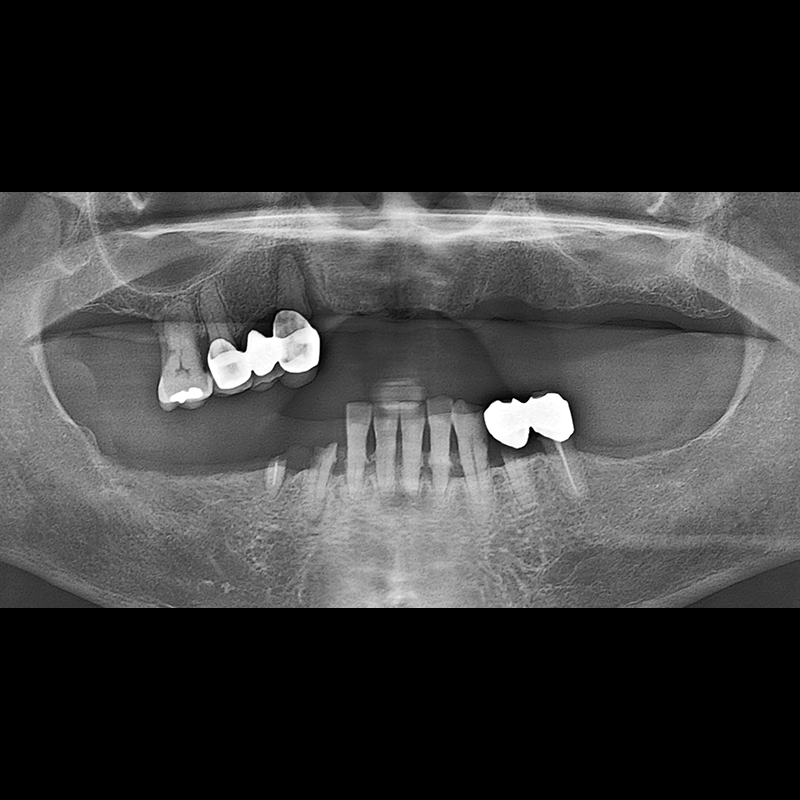

BEFORE AFTER

임플란트 전후사진 2025.05.30

결손된 치아 부분과 살리기 힘든 치아 위치에 임플란트를 식립하였습니다.